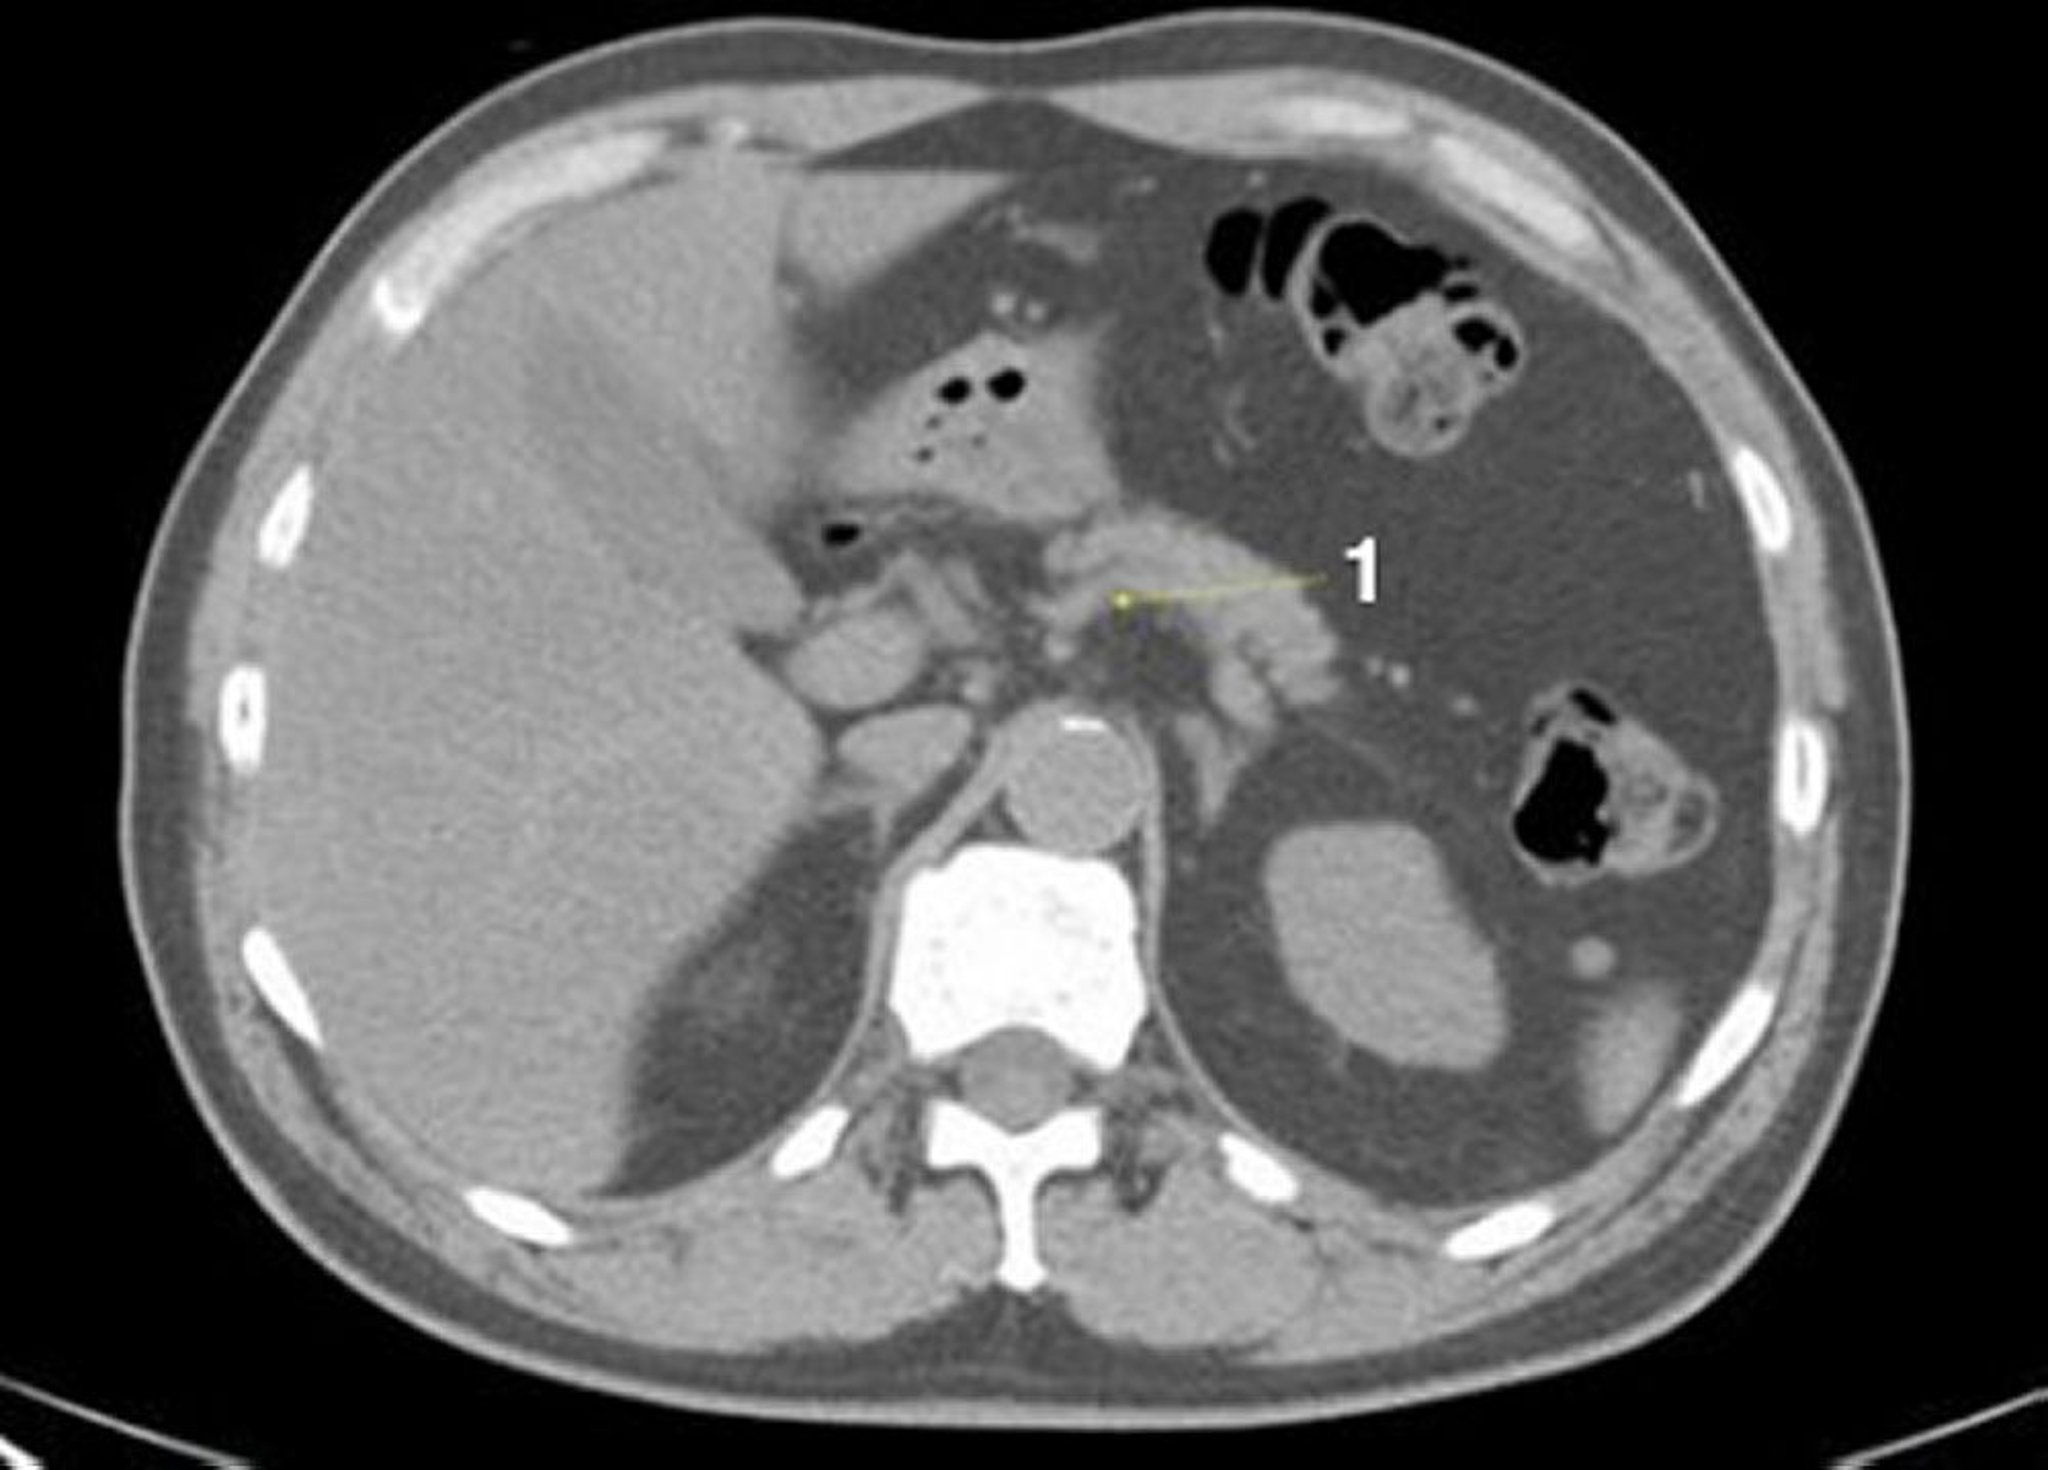

Tomografía computarizada sin contraste de abdomen y pelvis que muestra anatomía normal (corte 7)

1 = vena esplénica